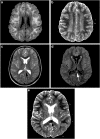

The authors present a case of acute disseminated encephalomyelitis in a COVID-19 pediatric patient with positive SARS-CoV2 markers from a nasopharyngeal swab. A previously healthy 12-year-old-girl presented with a skin rash, headache, and fever. Five days after that, she had an acute, progressive, bilateral, and symmetrical motor weakness. She evolved to respiratory failure. Magnetic resonance imaging (MRI) of the brain and cervical spine showed extensive bilateral and symmetric restricted diffusion involving the subcortical and deep white matter, a focal hyperintense T2/FLAIR lesion in the splenium of the corpus callosum with restricted diffusion, and extensive cervical myelopathy involving both white and gray matter. Follow-up examinations of the brain and spine were performed 30 days after the first MRI examination. The images of the brain demonstrated mild dilatation of the lateral ventricles and widespread widening of the cerebral sulci, complete resolution of the extensive white matter restricted diffusion, and complete resolution of the restricted diffusion in the lesion of the splenium of the corpus callosum, leaving behind a small gliotic focus. The follow-up examination of the spine demonstrated nearly complete resolution of the extensive signal changes in the spinal cord, leaving behind scattered signal changes in keeping with gliosis. She evolved with partial clinical and neurological improvement and was subsequently discharged.